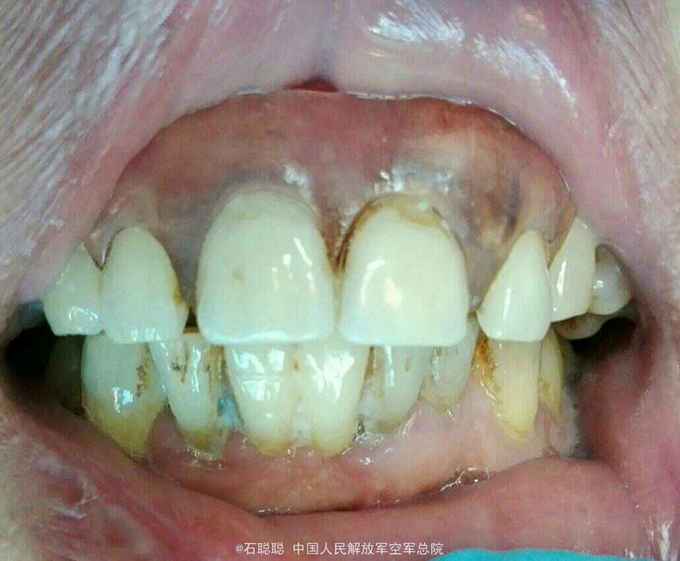

诊断:11、21缺失 治疗计划:向患者交代种植、活动、固定义齿修复方案的优缺点,患者考虑到种植周期长、活动修复难以满足美观要求,选择全瓷固定桥修复方案,但患者12、22基牙条件不甚理想,交代患者修复后要严密观察,定期复诊。 处置:12、13、22、23碧蓝局麻下开髓,拔髓,冲洗,置失活剂,氧化锌暂封 一周后复诊:去除暂封,测量根长,12=22=19mm,扩大至25#,13=23=24mm,扩大至35#,大量冲洗,干燥根管,置CP棉球,氧化锌暂封。 一周复诊:12、13、22、23去除暂封,试主尖,冲洗,干燥,冷测压充填,拍摄根尖片,恰填,置干棉球,氧化锌暂封 一周后复诊:12、13、22、23无不适,去除暂封,磷酸锌垫底,树脂充填,预备牙体,排龈,聚醚取模制作临时冠,调磨粘固 一周后复诊:试戴内冠,就位顺利,边缘密合 一周复诊:试戴全瓷桥,由于边缘密合,固位良好,调节正中咬合、前伸咬合、侧方咬合为轻接触,磨光U200粘固

讨论:在这个病历中,由于12、22牙槽骨有所吸收,并且缺牙区牙槽骨有一定量的丧失,这种修复方式并不推荐,但患者了解各种修复方式优缺点之后,强烈反对种植和活动修复,只能进行固定桥修复,治疗结束后除外嘱咐患者常规义齿戴总注意事项,一定要定期复查,观察基牙情况,防止牙槽骨进一步吸收。在制作义齿时,加工厂为补充缺牙区的牙槽骨吸收,龈端唇舌侧均补充了较多的瓷,可能会使得义齿视觉上比较大,这也是一种折中的做法。